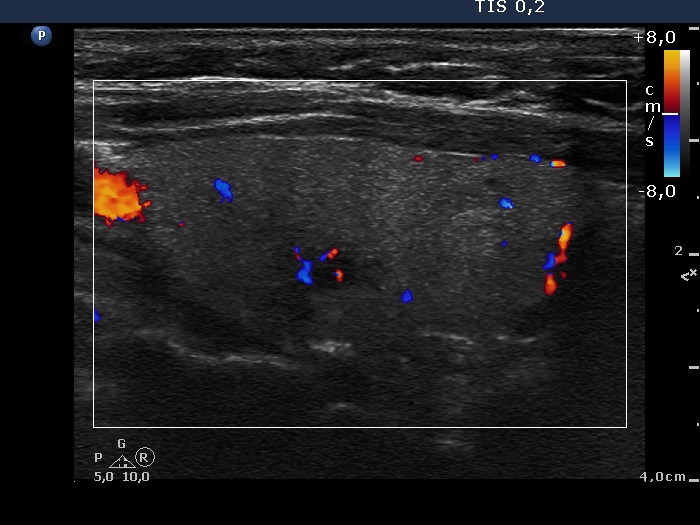

Intranodular hyperechogenic figures - case 1197 (ultrasonographic picture 3)

Right lobe, longitudinal scan, color Doppler mode. The vascularization is average.